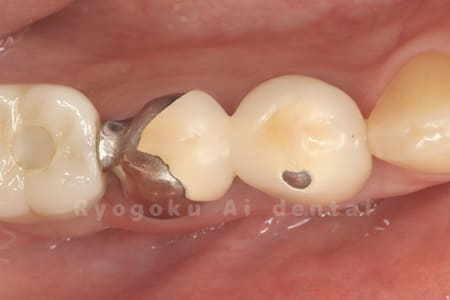

Case11

- 治療内容

- セラミッククラウン、セラミックインレー

-

- 治療費用

- 123,000円×2(セラミッククラン)、77,000円(セラミックインレー)

銀歯が取れて、ご来院された患者様です。奥歯2本をセラミッククラウン、手前の小臼歯をセラミックインレーで治療を行いました。

<リスク・副作用>

過度の咬合や衝撃で割れることがあります。